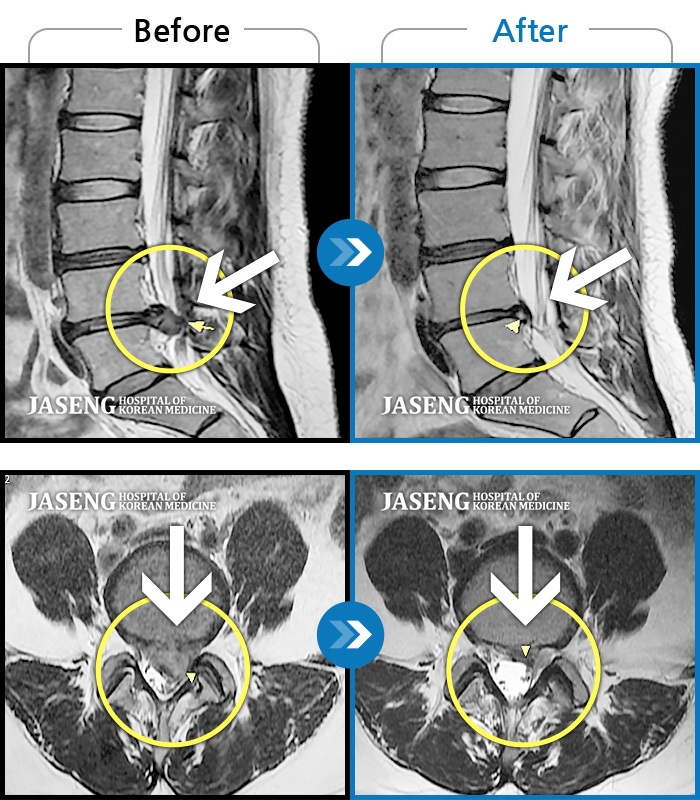

허리디스크

도움받은 사례

해운대 · 김상돈 원장

하지 저림과 통증이 개선되어서 일상생활이 너무 즐겁습니다.

촬영시기

2023.09.18 ~ 2025.01.27

2025.02.05

조회수 16,646